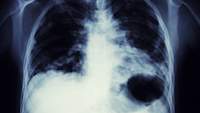

在肺癌筛查,医生使用了低剂量计算机断层扫描(LDCT)扫描,以测试为肺癌。你不需要有任何症状收到此测试;事实上,它通常用在人谁可能是这种疾病的高风险,但还没有表现出任何迹象。

这种扫描结合了多种x射线图像来创建一个身体的“切片”或横截面,显示骨骼、器官和软组织。单独的胸部x光检查不被认为是肺癌的有效筛查,也不推荐。事实上,根据最近的一项研究英国全科医学,标准x光片漏检肺癌的比例高达23%。

- 扫描仪内,使用高达90%的较少的辐射比传统的胸部X射线特殊的X射线将你的身体的多个横截面图像。

- 然后,计算机将这些图像合并成你肺部的超详细图像。